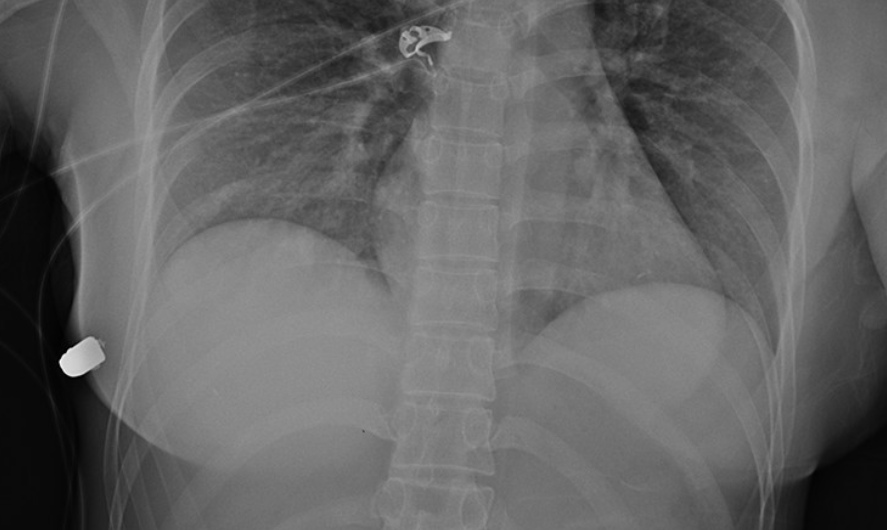

El equipo médico de un hospital local descubrió una herida de bala en la parte superior de su seno izquierdo. Las marcas de quemaduras alrededor de la herida indicaban que a la mujer le dispararon a corta distancia.

La bala se alojó bajo su pecho derecho, habiendo entrado en el pecho izquierdo, fracturando una costilla en el proceso, antes de detenerse en el lado derecho de su cavidad torácica.

Las pruebas hechas después de la operación revelaron solo daño en el tejido pulmonar, y mostraron que la bala había pasado por ambos implantes.

Tras una reconstrucción de la trayectoria de la bala a través del pecho de la mujer, el equipo médico concluyó que habría impactado en su corazón de no ser por el implante izquierdo.